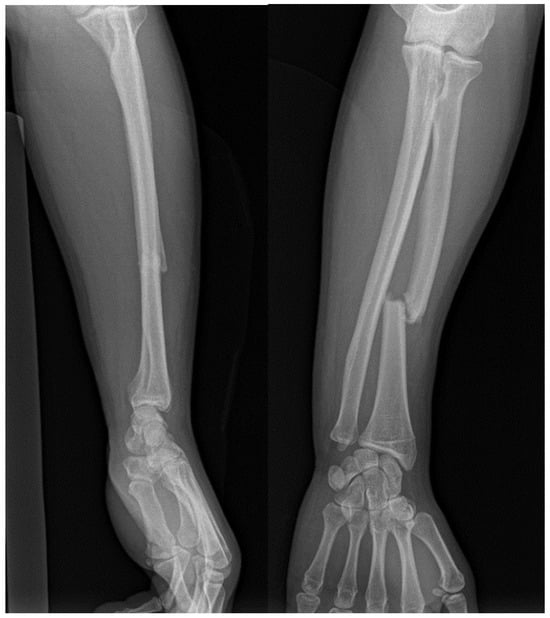

Galeazzi fractures involve a fracture of the radius and dislocation of DRUJ [7,61], comprising about 7% of forearm fractures and often resulting from high-energy trauma [11]. Symptoms include forearm swelling and deformity [62]. Various classification systems categorize these fractures based on their location relative to the DRUJ and radial styloid involvement [63,64,65]. In adults, radial shaft fractures with distal ulna fractures are termed Galeazzi equivalents [62].

Accurate diagnosis relies on X-rays or CT scans to evaluate the DRUJ and detect neurovascular damage, although radiographic predictors of instability may not always be reliable (Figure 6) [7,62].

Figure 6. AP and lateral views of a Galeazzi fracture.

Treatment typically involves surgical intervention, such as open reduction and internal fixation (ORIF) and DRUJ stabilization (Figure 7) [7,65,66]. Postoperative care includes immobilization and rehabilitation, depending on DRUJ stability [62,65,67]. Complications can include pain, stiffness, instability, malunion, nonunion, and rare neurovascular damage [58,61,62].